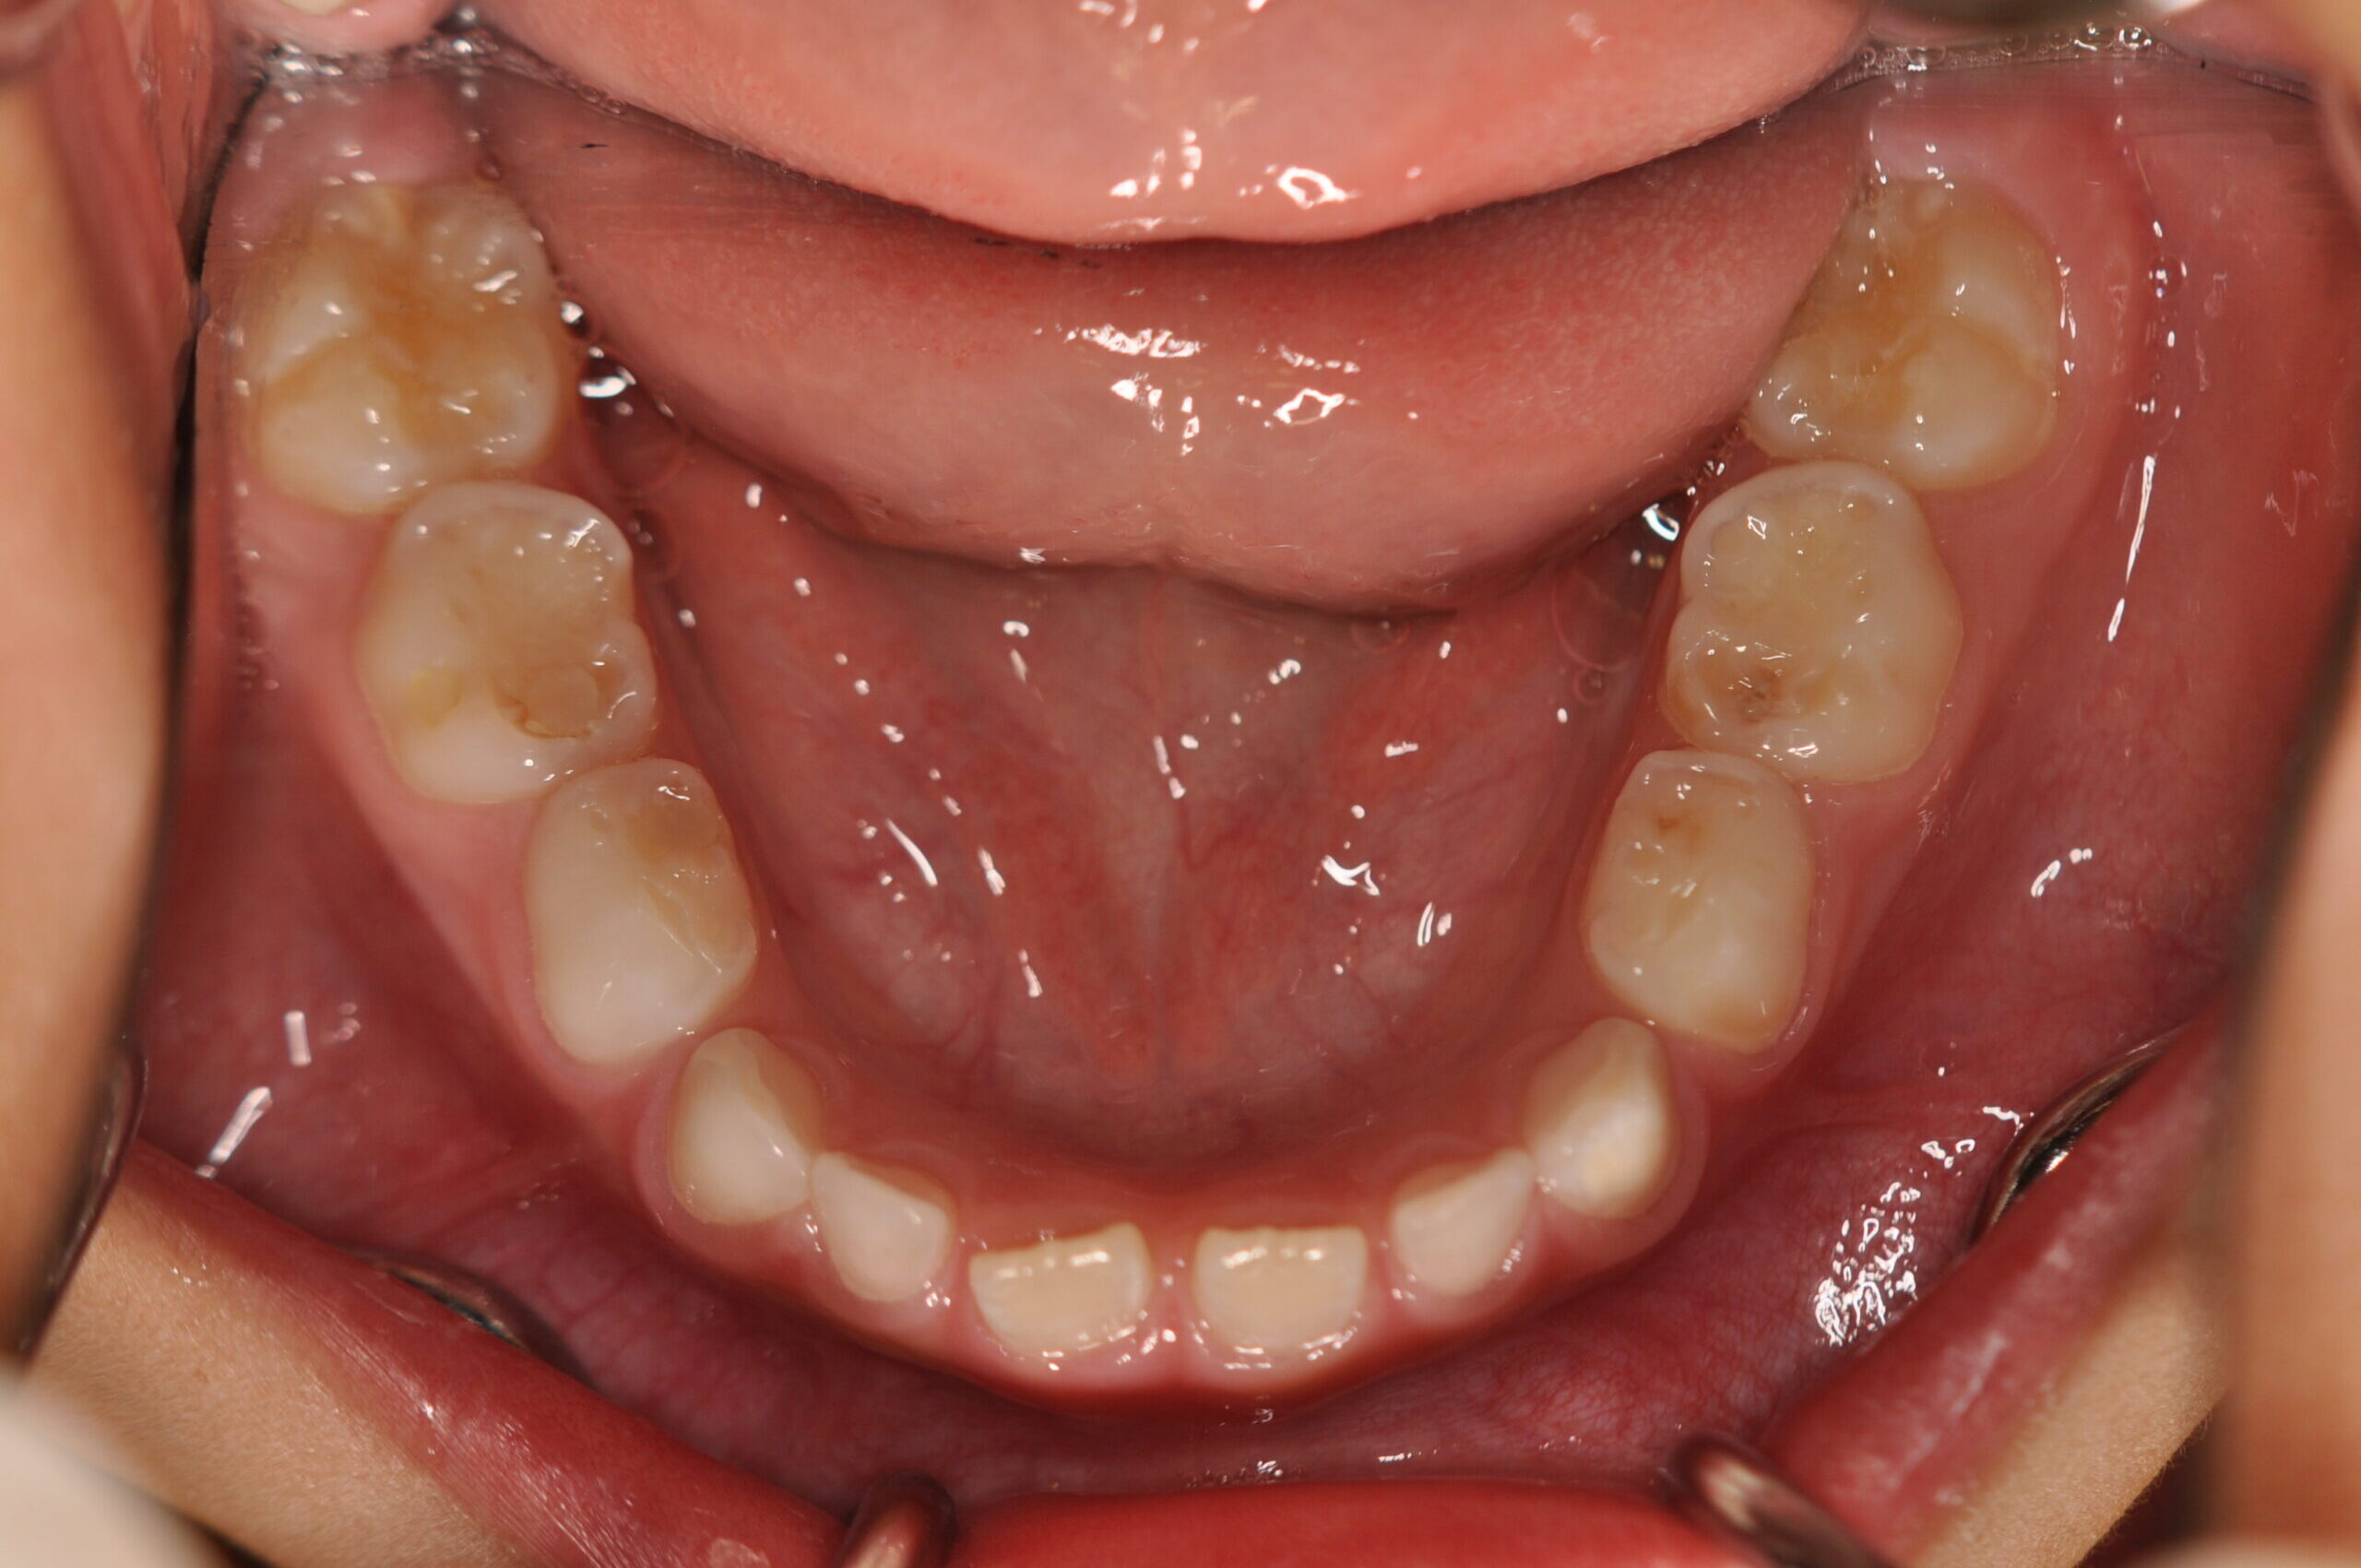

初診時

症例 症例 症例 症例

年齢

6歳0ヶ月 性 別 男性

治療内容の詳細 初診時6歳の男性で、受け口を気にされ来院されました。

検査の結果、反対咬合を伴うアングルⅢ級不正咬合と診断しました。